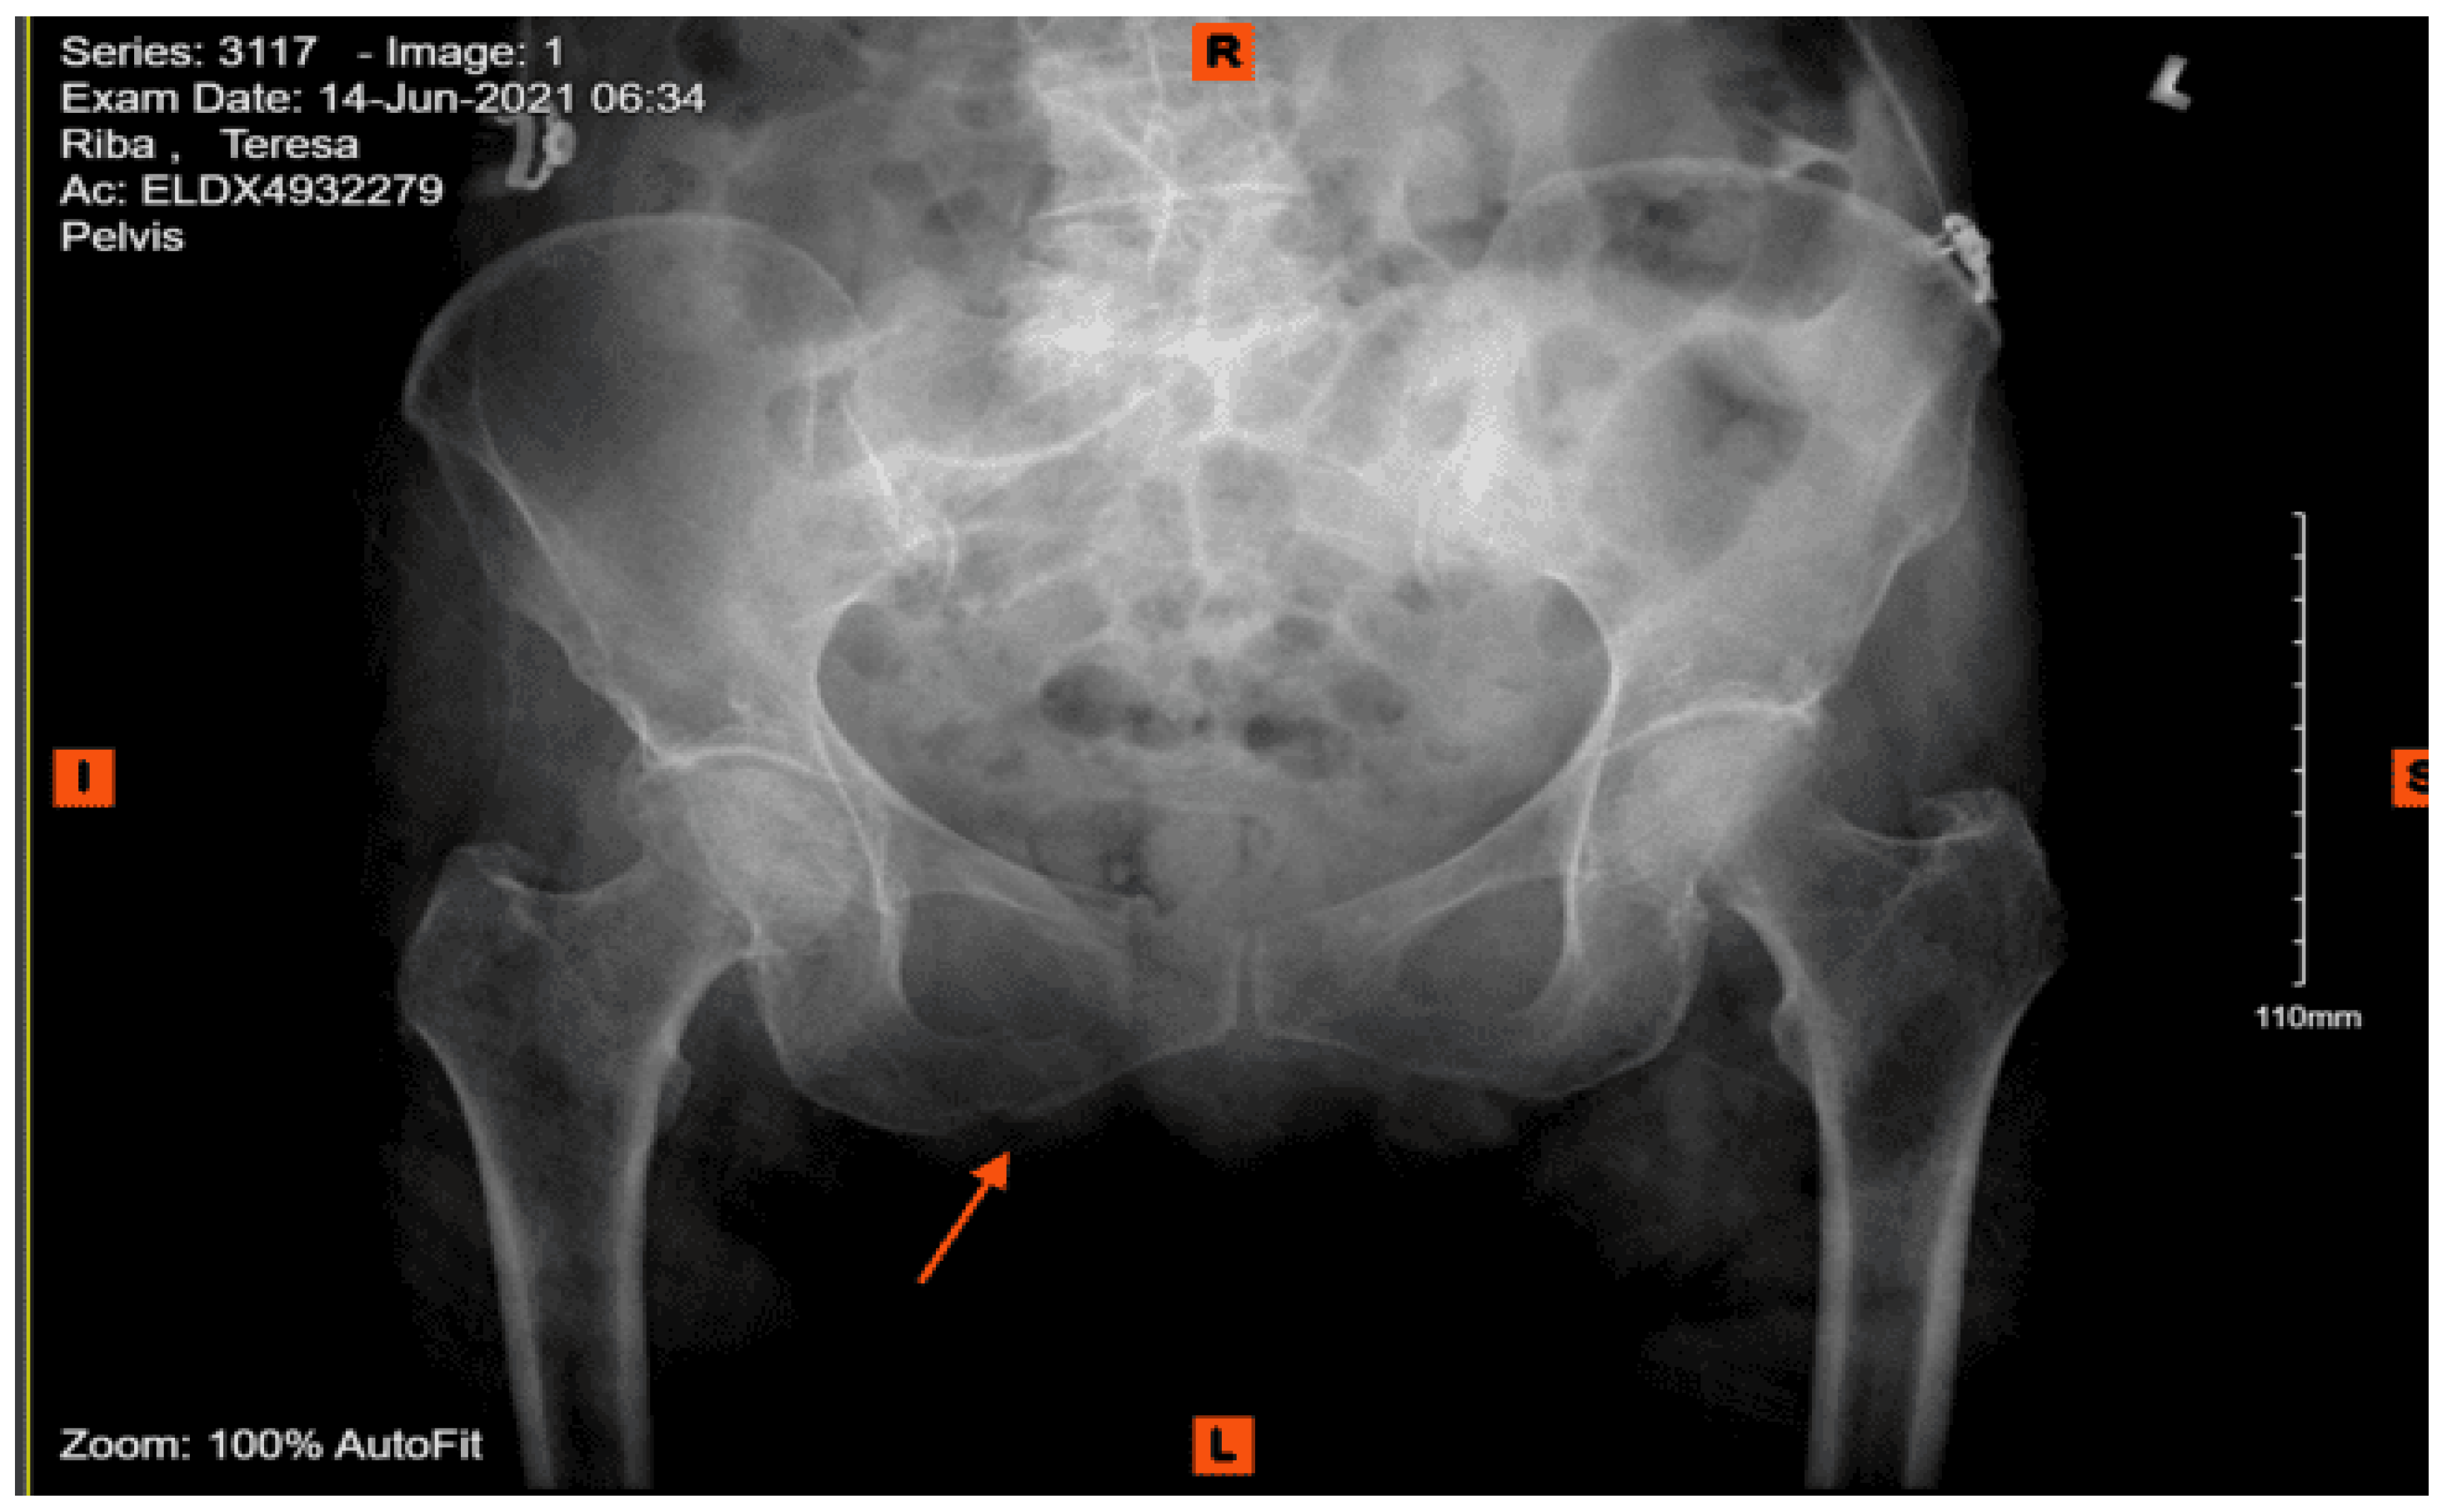

Imaging as shown in Figure 24, Figure 25 and Figure 26:

Portable chest X-ray: No pneumothorax. No pleural effusion. Osteopenia and degenerative changes of the dorsal spine.

Portable pelvis X-ray: Degenerative changes about both hips. Probable subcapital fracture of the right hip. Marked concentric narrowing of the joint space of the right hip. Osteopenia.

CT abdomen pelvis with contrast: Grossly intact abdominal and pelvic viscera with acute fracture of the left superior pubic ramus near the symphysis and the bilateral inferior pubic rami.

CT lumbar spine without contrast: Diffuse osteopenia of the lumbar spine with suggestion of a fracture involving the anterior aspect of the vertebral body of L5 in its superior portion and acute fracture of the anterior aspect involving the lateral mass of S1